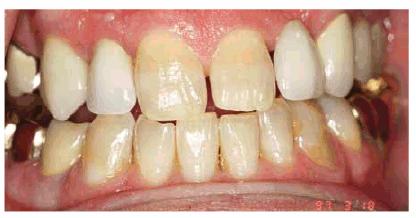

Figure 16-2A and B: Total neglect resulted in severe staining

of this patient's teeth.